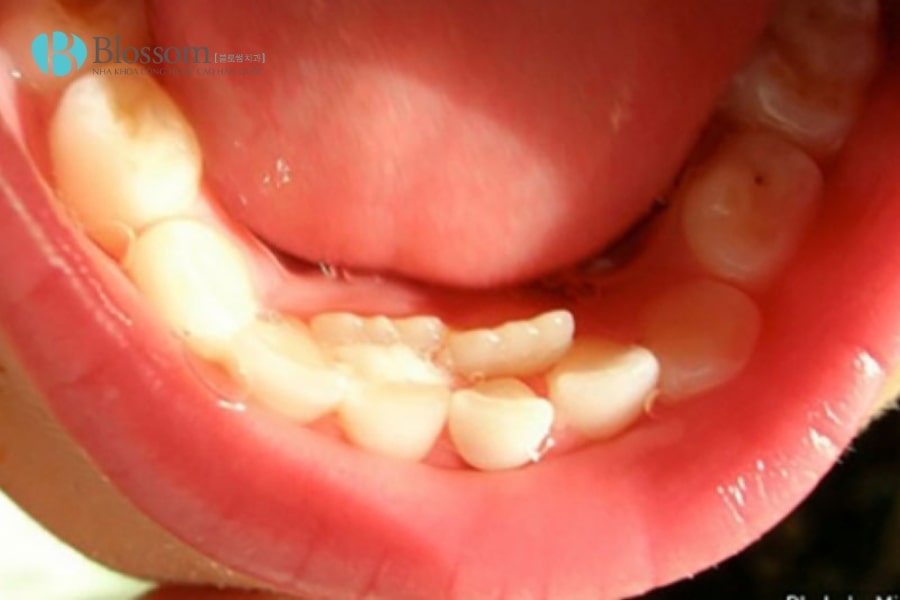

2.2. Mọc thừa răng ở hàm dưới

Răng thừa ở hàm dưới thường mọc bên cạnh các răng cửa hoặc răng hàm nhỏ, đôi khi chen chúc với răng vĩnh viễn. Dù ít gặp hơn hàm trên, nhưng nếu không xử lý sớm có thể gây lệch khớp cắn và ảnh hưởng thẩm mỹ.

Răng thừa ở hàm dưới thường mọc bên cạnh các răng cửa hoặc răng hàm nhỏ